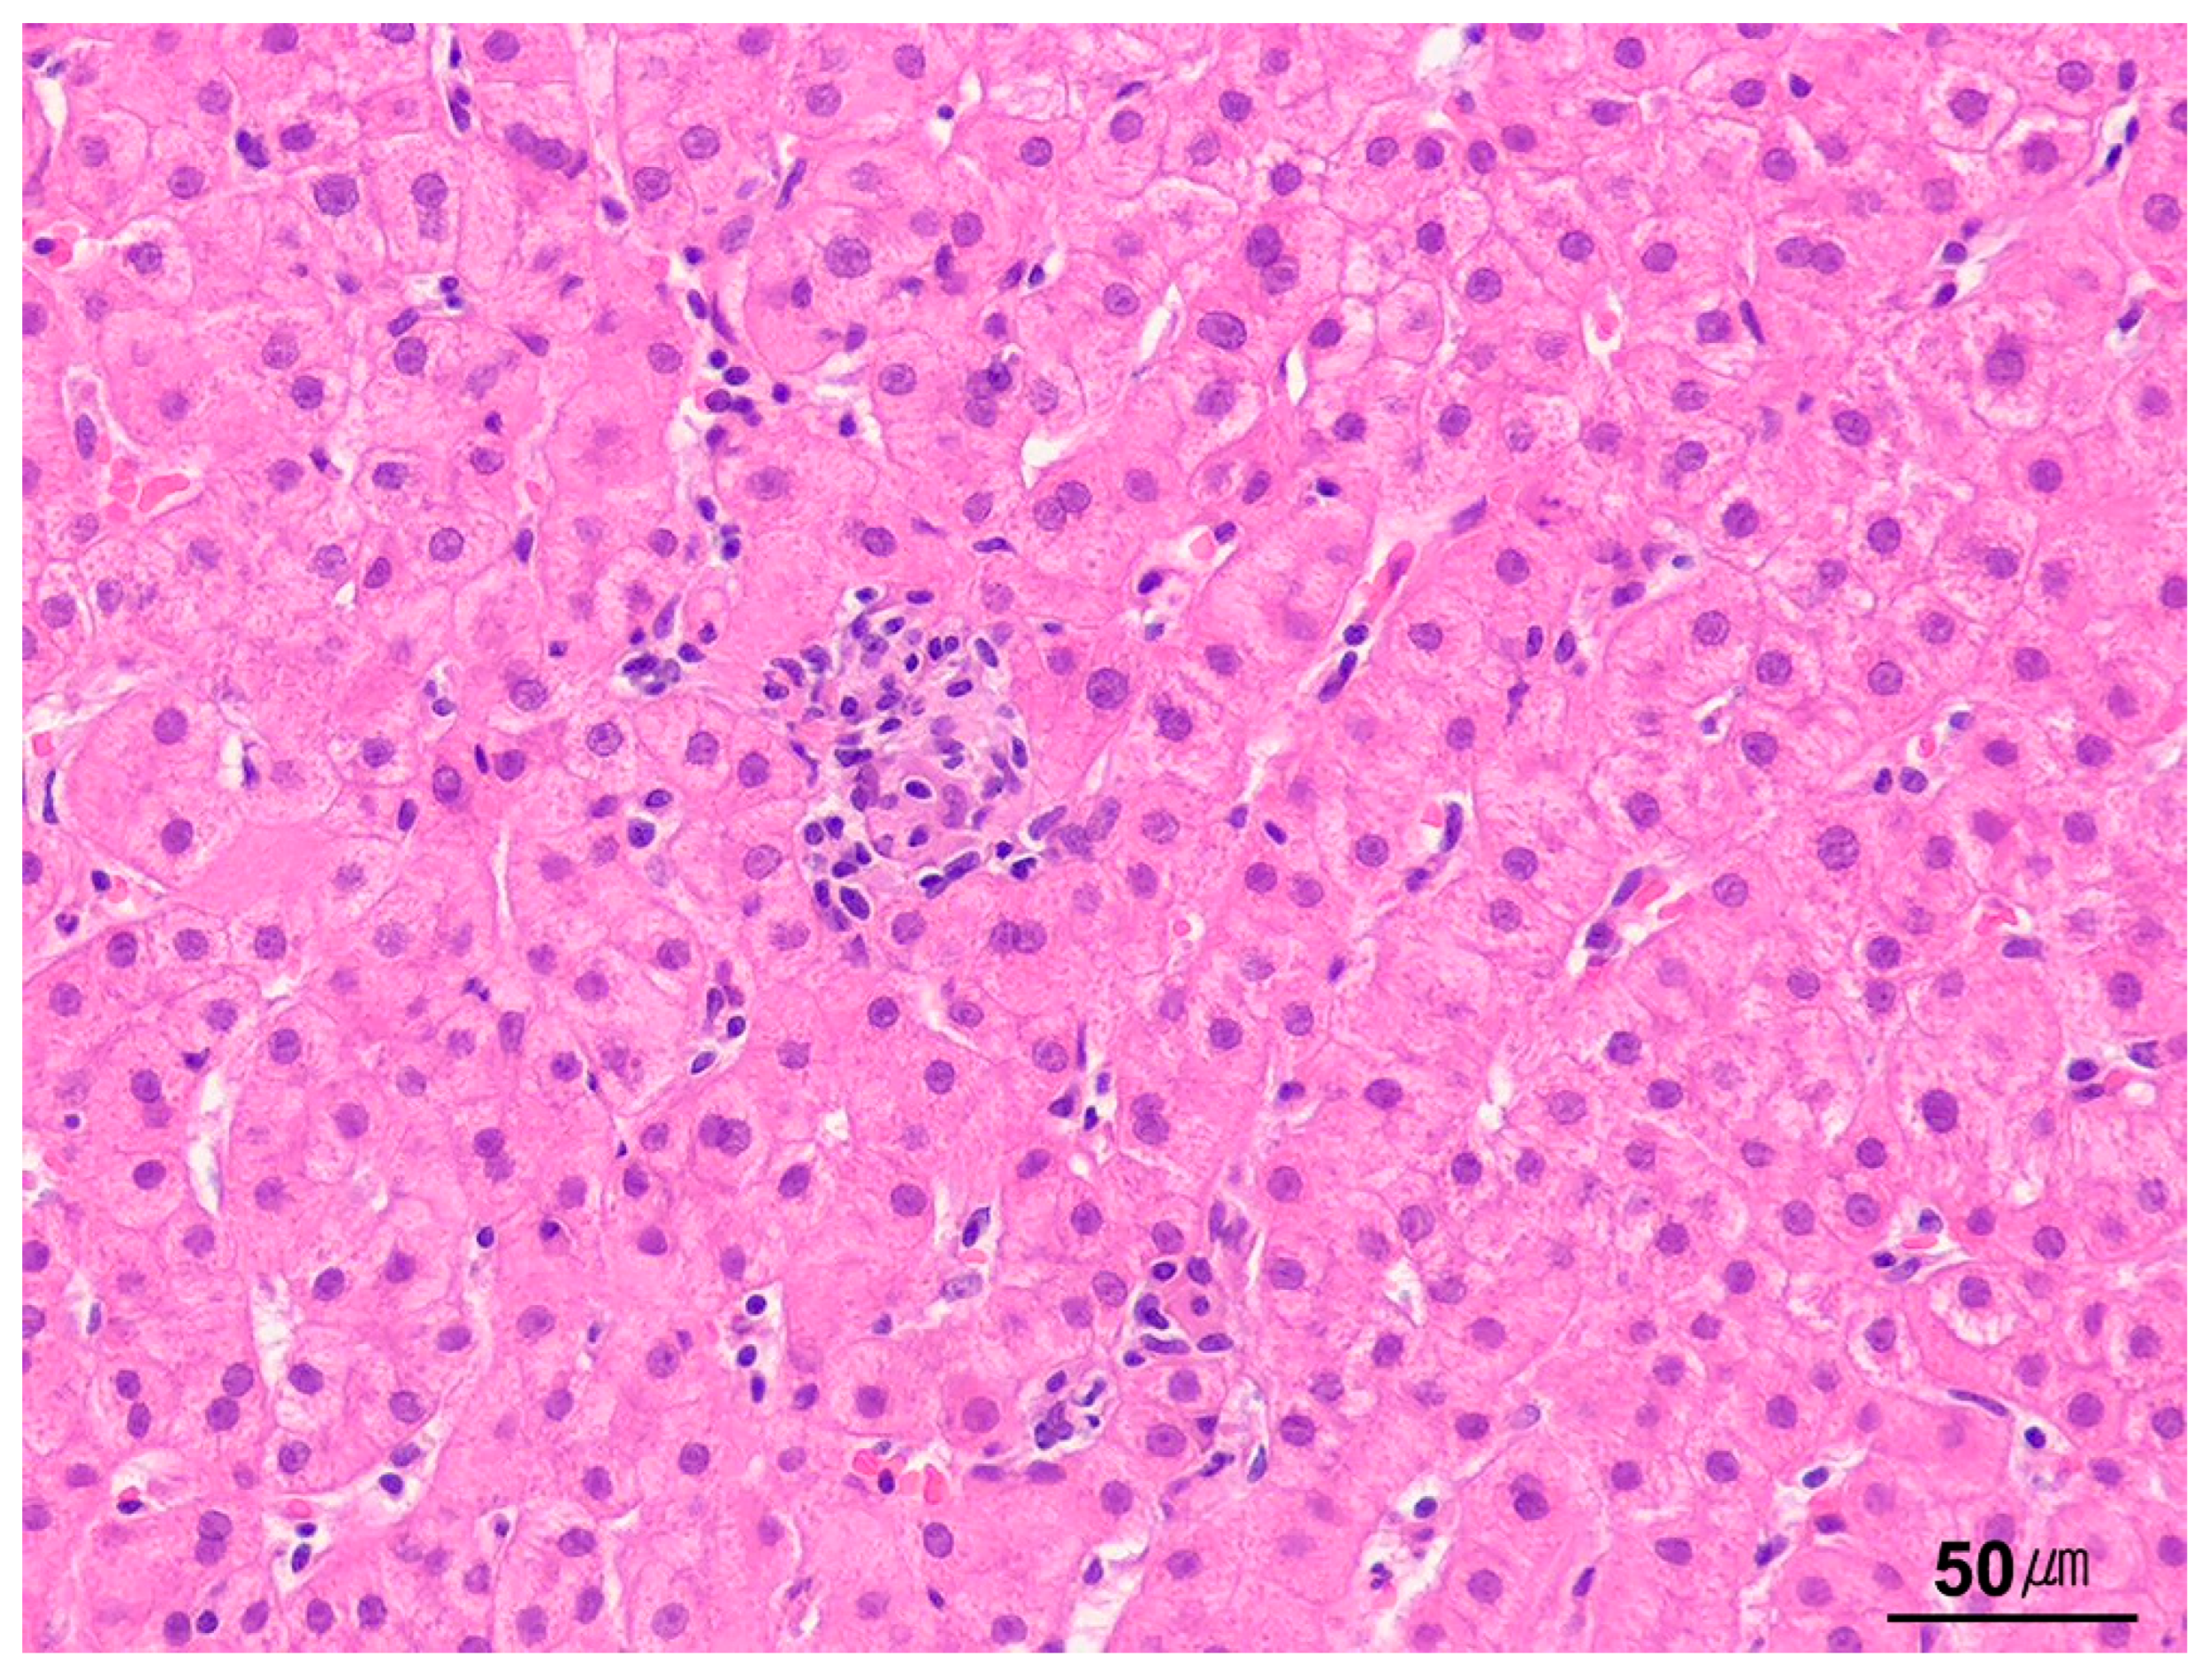

2. Normal Histology of the Liver